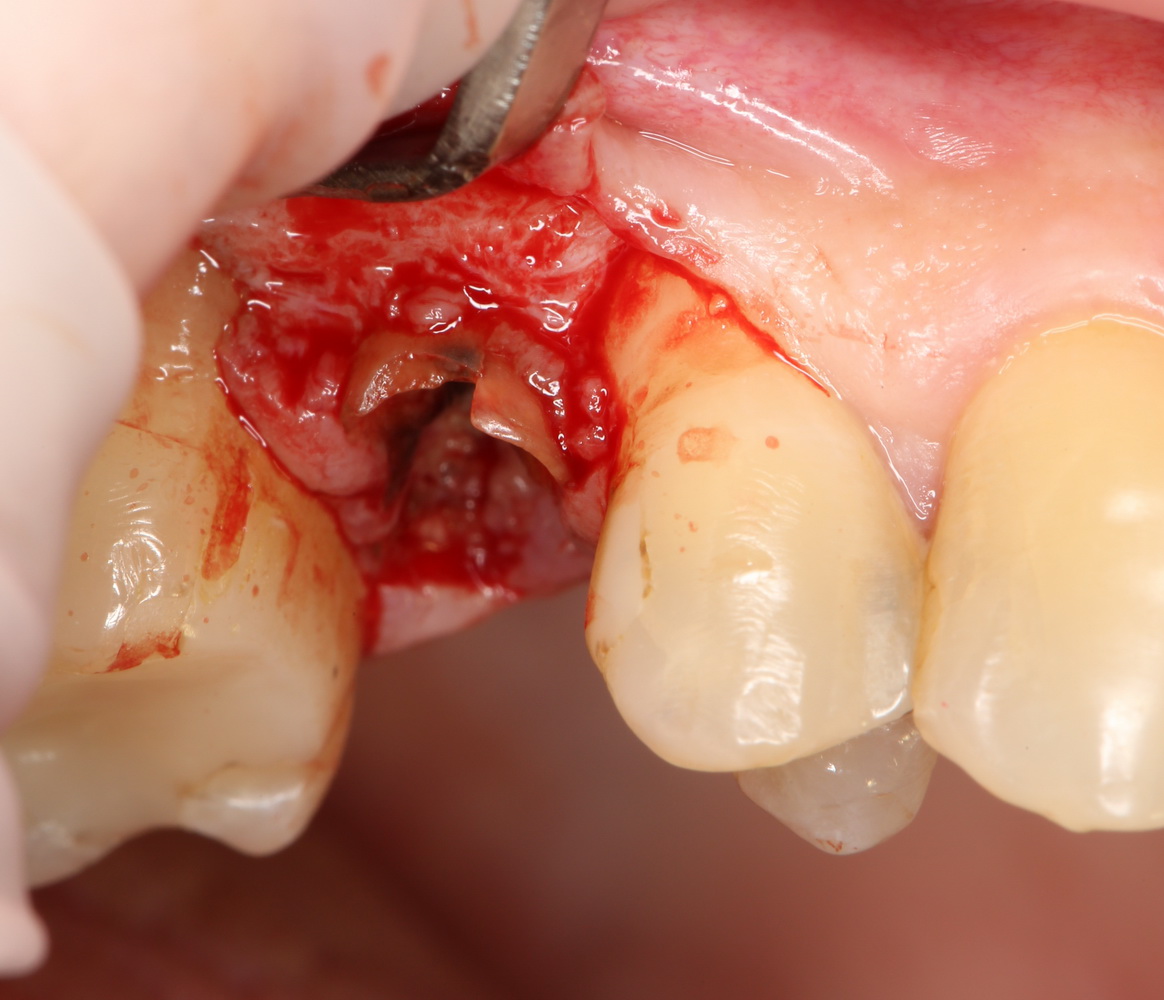

Ремарка: еще на этапе консультации с участием стоматолога-ортопеда, мы признали 44 зуб негодным и решили его удалить. Перед проведением разреза мы убрали коронку с 44 зуба и подготовили его к удалению. Так мы избежим попадания фрагментов коронки в открытую рану, а проведение самого разреза получится проще и аккуратнее.

Кстати, обрати внимание на ширину альвеолярного гребня (левая картинка). Она чуть меньше 3 мм. Это объясняет, почему я засомневался в возможности установки имплантатов одновременно с остеопластикой. Понятно и без КЛКТ.

Наперво, мне нужно удалить разрушенный зуб и получить костный аутотрансплантат.

Для получения костного блока, мы открываем донорскую зону, наружную косую линию нижней челюсти.